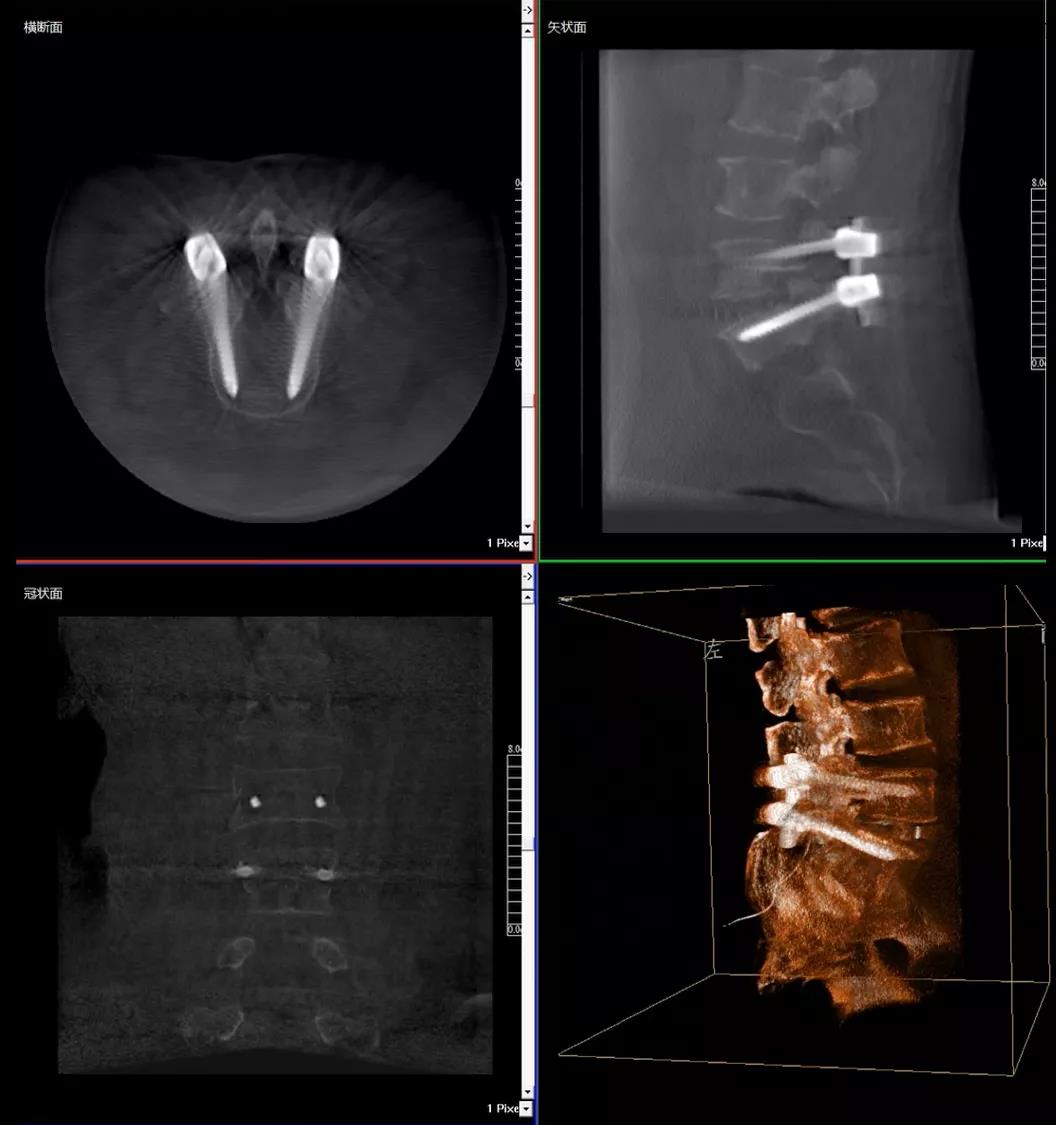

术中快速生成横断面、矢状面、冠状面断层图像和三维立体图像